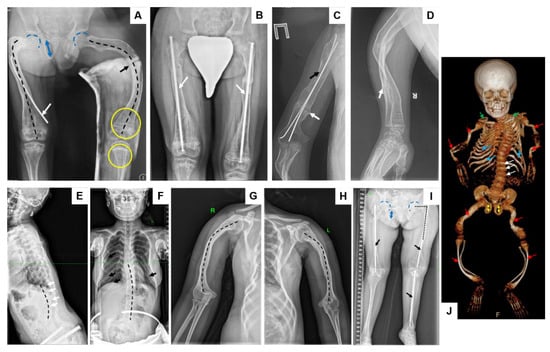

| Characteristic | Patient 1 | Patient 2 | Patient 3 * | Patient 4 * |

|---|---|---|---|---|

| Mutation | c.185G>T/c.992_993insCA | c.261_265dup (homozygous) | c.261_265dup (homozygous) | c.261_265dup (homozygous) |

| Ethnicity | Russian | Tuvan | Tuvan | Tuvan |

| Consanguinity | No | No | No | No |

| Age (years) | 23 | 3 | 16 | 12 |

| Sex | M | M | F | M |

| Age at first fracture (months) | 13 | 6 | 18 | 9 |

| Fracture sites 1 | 1, 2, 3, 4, 5, 6 | 2, 3, 4, 5, 6 | 1, 2, 3, 4, 5, 6 | 1, 2, 3, 4, 5, 6 |

| Fractures total (n) | 200 | 15 | 12 | 14 |

| Fractures/year | 8.69 | 3.0 | 0.8 | 1.27 |

| Scoliosis (grade) | IV | - | I | II |

| Severity of long bone deformities | Severe | Moderate | Moderate | Severe |

| Height (SD Score) | −5.52 | −2.73 | −2.96 | −7.71 |

| BMD (L1–L4) (g/cm2) | 0.592 | 0.874 | 0.874 | 0.256 |

| Z-score (L1–L4) | −3.1 | −1.7 | −1.7 | −4.6 |

| Blue sclera | No | No | No | No |

| Dentinogenesis imperfecta | No | No | No | No |

| Hearing loss | No | No | No | No |

| Age at initiation of bisphosphonates | 6 years | 1 year 8 months | 8 years | 6 years |

| Independent walking | No | No | No | No |